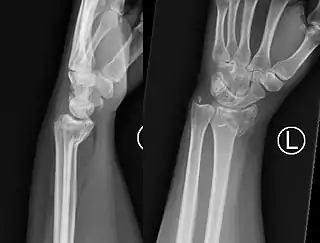

Fractura de Smith muñeca izquierda

El fragmento de fractura distal se desplaza de forma volar (ventralmente), a diferencia de la fractura de Colles, que el fragmento se desplaza dorsalmente. Dependiendo de la gravedad del impacto, puede haber uno o varios fragmentos y puede o no afectar la superficie articular de la articulación de la muñeca.

El diagnóstico inicial es clínico mediante al exploración, haciendonos sospechar la presencia de este tipo de fractura si se presentan los signos detallados arriba. Ante esta sospecha, el diagnóstico final apropiado de este tipo de fracturas necesita la realización de una radiografía simple del antebrazo distal y del carpo en al menos dos proyecciones: antero-posterior y lateral. En algunos casos, una vez realizada la radiografía simple, cuando las imágenes muestren que se trata de una fractura multifragmentario o compleja, la realización de una tomografía computarizada simple de la lesión puede ser útil para guiar el tratamiento.